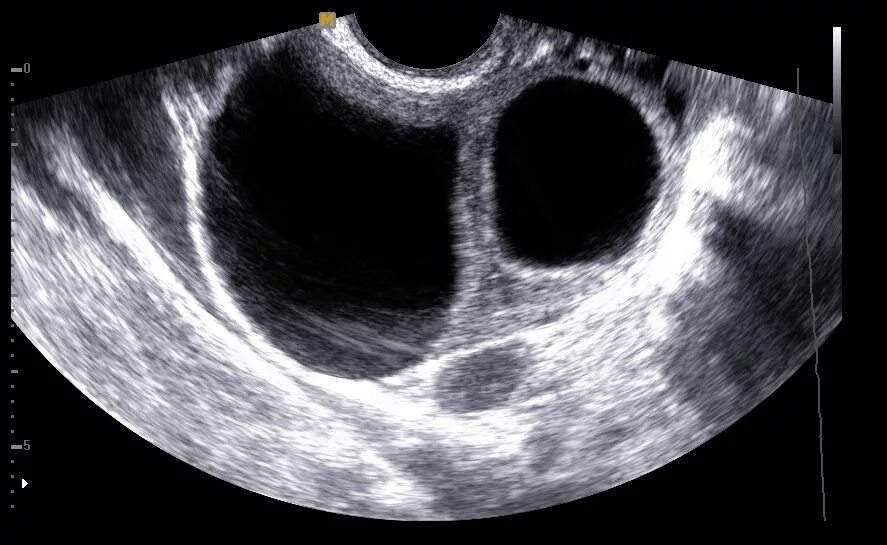

Аномальная беременность